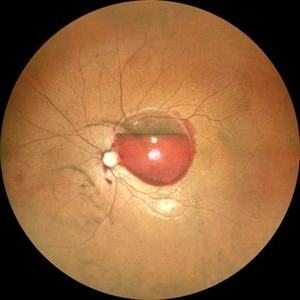

Von Hippel-Lindau Syndrome

Color photo montage of a 19-year-old female with Von-Hippel-Lindau syndrome.

Photographer: Dr. Akansha Sharma-Retina Foundation, Ahmedabad

Condition/keywords: angioma, Von Hippel-Lindau